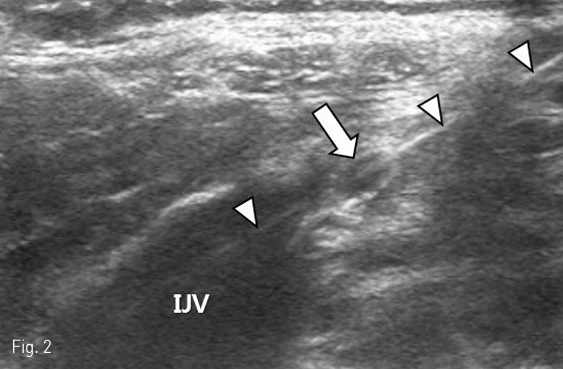

After sterile preparation of the neck and left chest wall, local anesthesia of the skin and subcutaneous tissue overlying the left internal jugular vein was performed by injecting lidocaine 2%. The left internal jugular vein was then punctured with a 19-guage needle under ultrasound guidance and a 0.035-inch guide wire with a J-tip was passed through the needle bore and directed into the right atrium under fluoroscopy. After creating a subcutaneous pocket in the left subclavian fossa which would harbor the infusion port, a tunneling device that attached to the infusion catheter was advanced through the subcutaneous layer from the pocket towards the venous access site. Following the tunneling maneuver, a stream of “milky”fluid was seen to spill out of the skin at the point of venous access (Fig. 1). This fluid was immediately recognized to be chyle and ultrasound was used to reveal the course of the guide wire traversing the cervical portion of the thoracic duct (Fig. 2). Before foregoing aggressive intervention, conservative management was attempted by manual compression after guide wire removal. In line with our expectations, stasis of chyle spillage was achieved with light compression for ten minutes. In order to complete the chemoport placement procedure, a new access was created in the left internal jugular vein, albeit a little more cephalad to the original puncture site. The chemoport was finally placed without complication.

Fig 2

Ultrasound demonstrating the thoracic duct (arrow) between the left internal jugular vein (IJV) and vertebral vein (VV). A guide wire (arrowheads) penetrating the thoracic duct is noted.

The true incidence of lymphatic injuries during central venous catheterization is unknown owing to the rarity of such complications. This is reflected by the scarcity of literature which is limited to isolated case reports [2-6]. Although fluid analysis was not performed in our case, the characteristic “milky”appearance of chyle was suggestive of thoracic duct injury and this was correlated on ultrasound. The thoracic duct is the largest lymphatic vessel in the body and drains almost of the body’s lymph. It is the common trunk for all the lymphatic vessels of the body, excepting those on the right side of the head, neck, and thorax, the right upper extremity, right lung, right side of the heart, and the convex surface of the liver. The thoracic duct usually terminates at the junction of the left internal jugular vein and left subclavian vein, a site that is commonly referred to as the jugulovenous angle [7,8]. In our case, ultrasound demonstrated the guide wire which had penetrated the cervical portion of the thoracic duct. The cervical portion of the thoracic duct is an anatomical landmark where the thoracic duct passes up and over between the left internal jugular and vertebral veins before it joins the jugulovenous angle. High-resolution ultrasound imaging with linear probes have been shown to be useful for visualizing the portion of the thoracic duct [9]. Although the use of ultrasound guidance has been shown to reduce the risk of complications that potentially occur during central venous catheterization, the presence of the thoracic duct may be overlooked without special attention. With regard to left-sided central venous catheterization, scrutiny during ultrasound guidance is mandatory, not only to avoid vascular complications, but also lymphatic injury. Interventional radiologists who commonly perform ultrasound-guided venous access in the neck region should be familiar with the anatomy of the thoracic duct and how it appears under ultrasound.